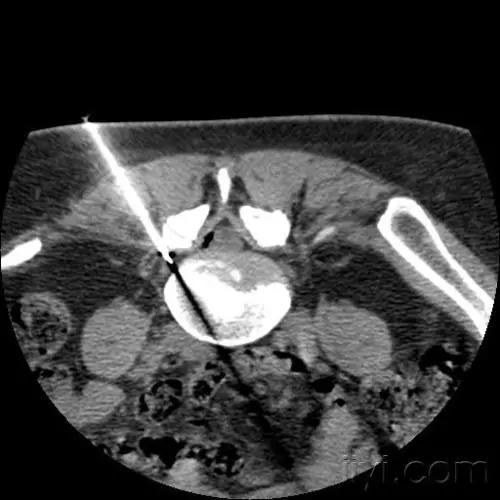

选择性神经根阻滞(特色技术)

该手术是在可视化超声或者CT引导下将穿刺针经椎间孔穿刺到病变神经根处,松解粘连的神经根和硬脊膜囊。对缓解腰椎间盘突出症的神经根性疼痛有显著疗效。通过一次选择性神经根松解阻滞术,既可缓解患者腰腿痛症状,又可定位引起患者疼痛症状的神经根节段,明确诊断,为后期行开放性手术精准定位了责任节段,可谓“一石二鸟”。